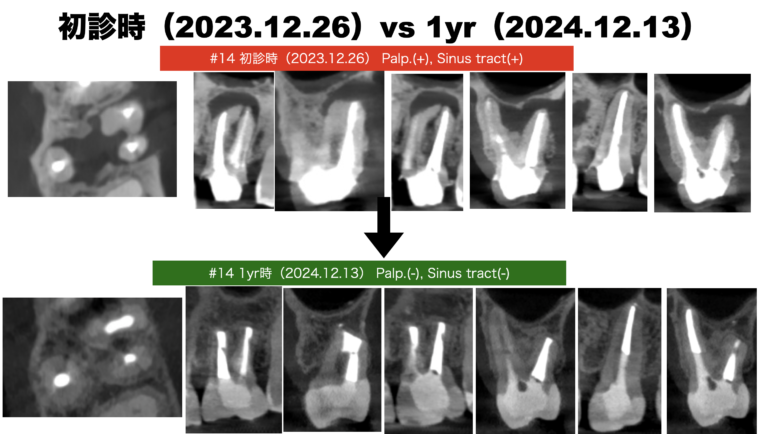

歯内療法学的検査(2023.12.20)

#30 Cold+3/2, Perc.(-), Palp.(-), BT(-), Perio Probe(WNL), Mobility(WNL)

#31 Cold N/A, Perc.(+), Palp,(-), BT(-), Perop Probe(WNL), Mobility(WNL), Sinus tract(+)

歯内療法学的診断(2023.12.20)

Pulp Dx: Previously treated

Periapical Dx: Chronic apical abscess

Recommended Tx: Re-RCT